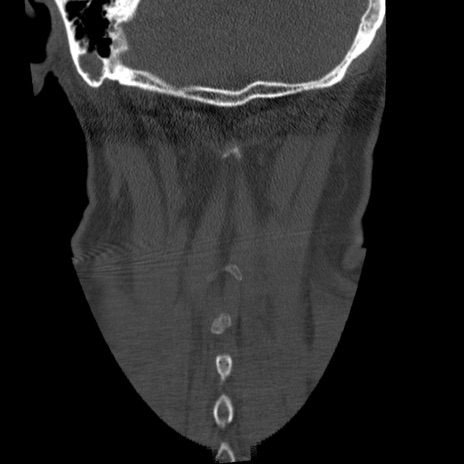

症例50 頚椎CT(冠状断像)

横断像